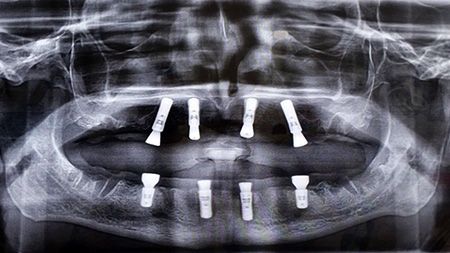

Straumann Pro Arch

L'ortopantomografia fatta dopo l'intervento dimostra le posizioni degli impianti inseriti.